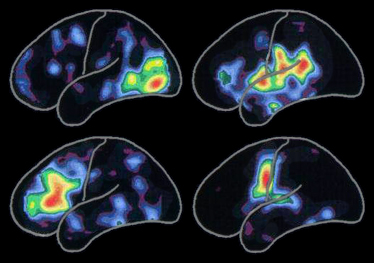

7. シグナルのコード化

左の陽電子断層撮影法(PET)スキャンは、以下に関連する脳の活動の標準的なパターンを示します。

活動は、赤の領域で最高潮に達し、黄色から青紫の他の虹色に変化するにつれて、減少します。

特定の活動パターンは、新しく人と知り合ったり、新たな経験をしたり、新しいスキルを獲得したりしながら、生涯にわたって変化します。また、このパターンは、アルツハイマー病または関連疾患が神経細胞や結合を次々に破壊するときも変化します。